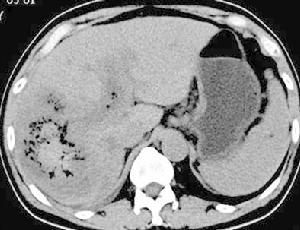

1.微粒栓塞治療巨塊型肝癌伴雙肺多發轉移

2.微粒栓塞治療巨塊型肝癌伴門靜脈主幹及左右支癌栓